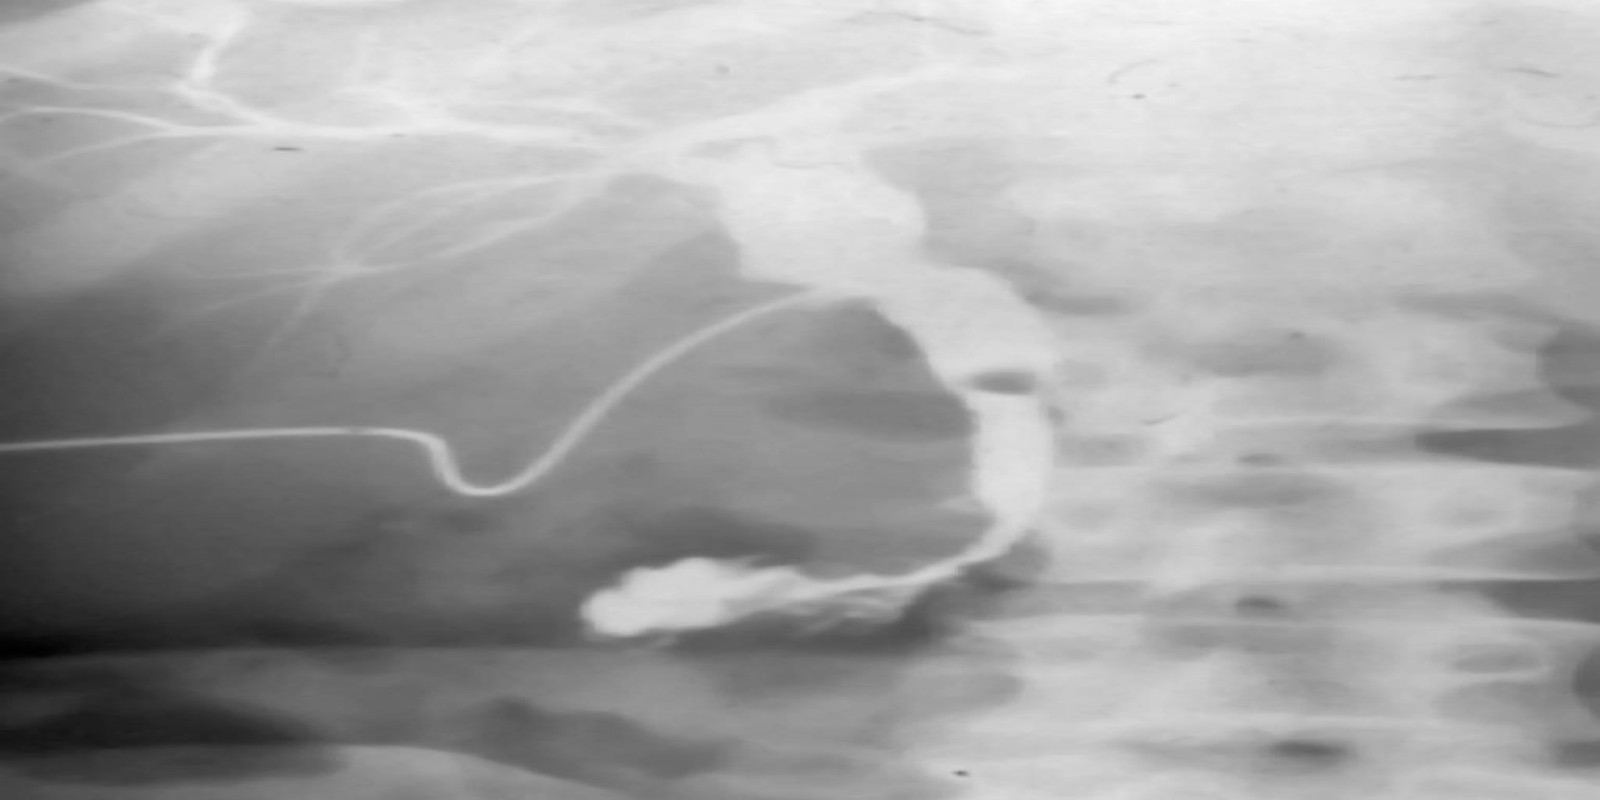

Caso Código 051A de Coledocolitíase

Cod.: 051A